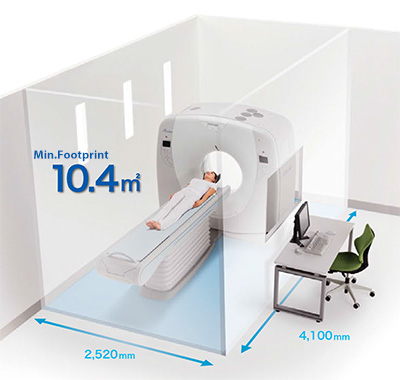

Серия Alexion отличается высокой производительностью и требует небольших помещений, так как имеет площадь всего 10,4 м2. Частично благодаря гибким требованиям к размещению, серия Alexion может быть запущена и работать в удивительно короткие сроки.